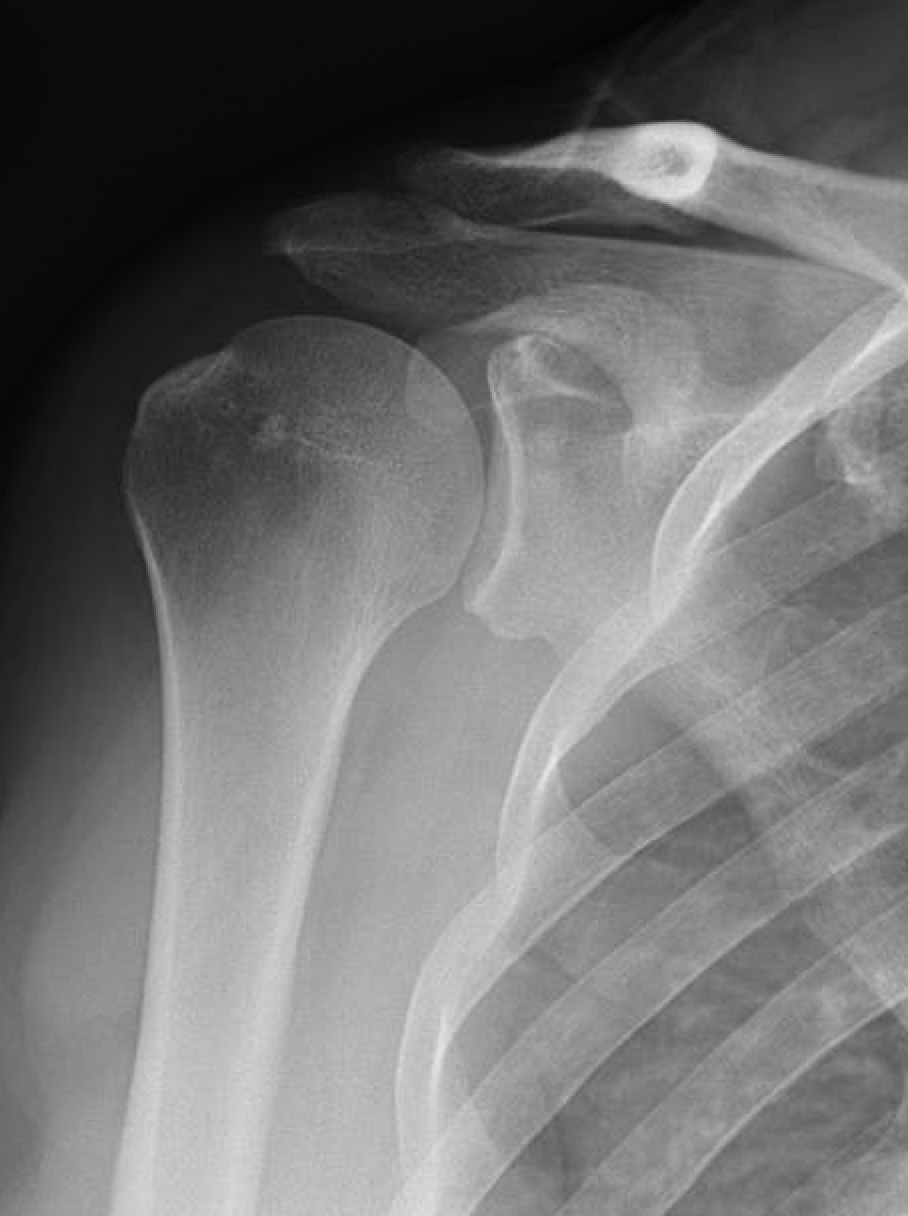

Rotator Cuff Tear Repair Phoenix Spine & Joint